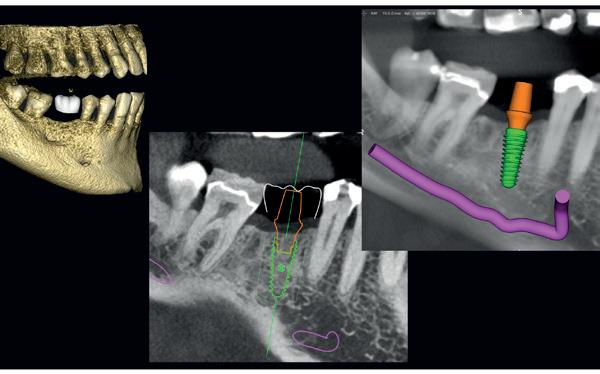

Voor het implantologisch onderzoek werd een CBCTscan (Trium CBCT, Acteon Frankrijk) vervaardigd van de edentate bovenkaak en in de software werd een planning gemaakt van 6 implantaten in de bovenkaak. De kaak kan opgedeeld worden in het front, tussen de 13 en 23 en de zijdelingse delen van de 14 t/m 17 en 24 t/m 27. Er dienen 2 implantaten in het front geplaatst te worden en 2 implantaten in de zijdelingse delen rechts en links, om een optimale verdeling van de implantaten (implant spread) te krijgen. De implantaten in deze casus werden gepland op posities 12, 22, 14, 24, 16 en 27. Tevens werd rekening gehouden met de krachtenverdeling óp de implantaten, deze zijn naar dorsaal toe forser dan in het front, daarom werd er gekozen voor brede implantaten (meer dan 5.0 mm in diameter) distaal en 4.0 mm diameter implantaten in het front. Voor de 16 was een crestale sinusbodemelevatie nodig en de 14 benodigde een kaakverbreding en verhoging.

Om de implantaten op de juiste vooraf geplande positie te implanteren, zijn er een aantal mogelijkheden (afbeelding 1 en 2). Eén daarvan is om de chirurgie guided uit te voeren, maar dat is lastig omdat de guide niet op elementen afgesteund kan worden. De guide dient dan met guide pins vastgeschroefd te worden, maar dat heeft als nadeel dat bij verplaatsing van de guide de implantaten niet op de juiste positie staan. Bij immediaat implanteren kan tegenwoordig gebruikgemaakt worden van meerdere stac-

1. Edentate maxilla

2. Planning in de CBCT-software Acteon AIS

kable guides, die op een base guide geklikt kunnen worden. Een tweede methode is om op basis van de CBCT-scan in de mond uit te meten waar de implantaat locaties zijn en door te kijken naar referentie van de onderkaak. In deze cases werd besloten om de implantaten vrij uit de hand te plaatsen.